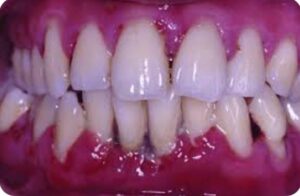

– Si kalon infeksioni nga goja në gjak Sëmundjet periodontale,si gingiviti dhe periodontiti ,shkaktohen nga baktere të cilat grumbullohen rreth mishrave dhe dhembëve .Kur mishrat janë të gjakosura dhe të inflamuara,këto baktere futen në qarkullimin e gjakut dhe nëpërmjet tij shkojnë në organet e tjera !

-Lidhjet me sëmundjet e zemrës: Bakteret orale dhe inflamacioni kronik ndikon në: